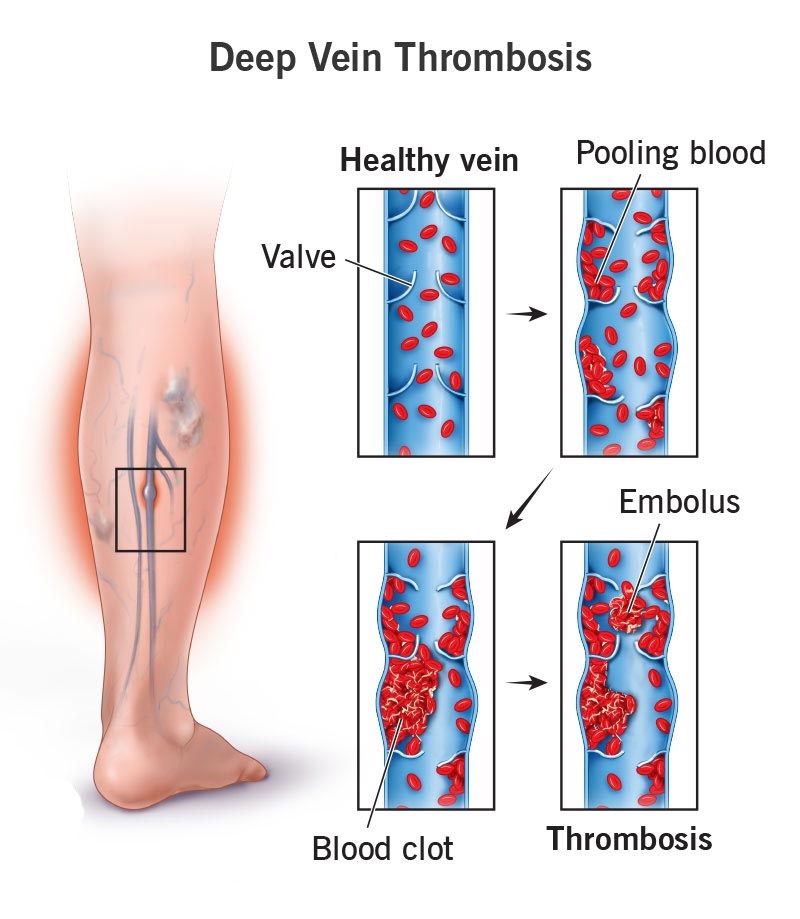

Venous Thromboembolism